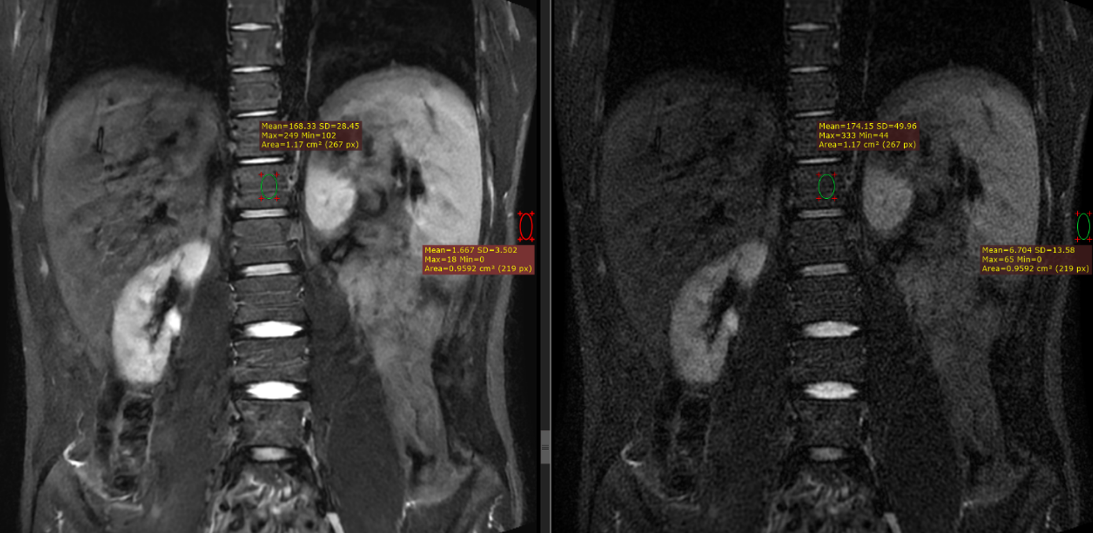

Representative spine images of coronal T2 weighted fast spin echo pulse sequence with an additional inversion pulse to null the signal emanating from fat are shown in Figure 2. An SNR improvement of 388% was realized.

Figure 2. Coronal T2 STIR fast spin echo image, acquired with a field of view of 32 cm. SNR gains of 388% were noted, when the final image was reconstructed through the deep learning-based reconstruction pipeline (left), compared to the image reconstructed conventionally (right).